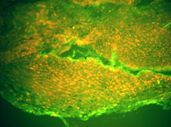

La Inmunofluorescencia Directa (IFD) realizada en la Cátedra de Dermatología del Hospital de Clínicas mostró: Ig. G depósito lineal altamente positivo en la membrana basal del epitelio (Fotos 6 – 7). Ig A: depósito en la capa basal. (Foto 8). C3: presente en la capa basal.

Foto 6 Foto 6 IFD: presencia lineal de IgG

Foto 7. IFD: Presencia lineal de IgA

Foto 8 IFD: positividad lineal para C3